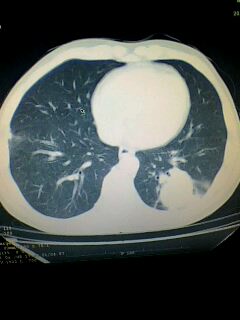

标题: CT28315:咳嗽咳痰咯血半月并胸痛 [打印本页]

标题: CT28315:咳嗽咳痰咯血半月并胸痛

1、纵膈窗效果不好,初步考虑左肺下叶感染性病灶,建议正规抗炎治疗后复查   2、右肺下叶陈旧性病灶伴局部胸膜增厚。

考虑左肺下叶周围型肺癌.图象欠清,请问病人贵更?

考虑左肺下叶周围型肺癌.

图像资料欠清,建议强化,考虑周围型肺癌。

左下肺肿块影,深分叶,考虑肺癌。

左下肺球形病灶,考虑:1:球形肺炎;2:周围型肺癌不除外,建议治疗后复查

不排除左肺下叶周围型肺癌可能!建议穿刺活检!

考虑左肺下叶周围型肺癌并阻塞性肺炎。